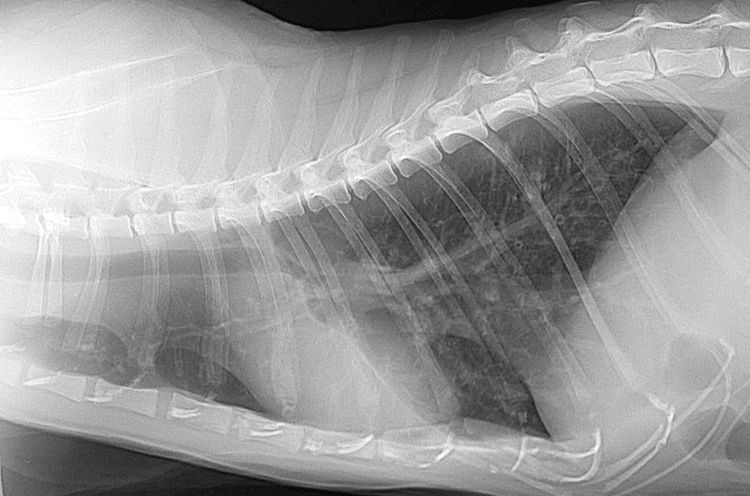

- Radiographie thoracique. En cas d'asthme chronique, les radiographies peuvent révéler un épaississement des parois bronchiques et/ou une distension du diaphragme.